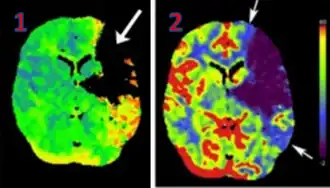

CT perfusion with flow and volume maps in cerebral infarction

Perfusion CT or CT Perfusion is a type of perfusion scanning using computed tomography. It is helpful in the evaluation of the vascularity of tissue in the body. In this, the temporal changes in tissue density are measured, providing information about the vascularity of the tissue. In CT perfusion, a contrast media injection is given, and then the scan is taken. The acquired data are post-processed to obtain perfusion maps with different parameters, such as BV (blood volume), BF (blood flow), MTT (mean transit time), and TTP (time to peak).[1][2]

CT Perfusion plays an important role in the assessment of Acute Ischemic Stroke. It is used to create maps of blood flow, blood volume, and mean transit time to assess the tissue and to differentiate between the core and penumbra in stroke.[3]